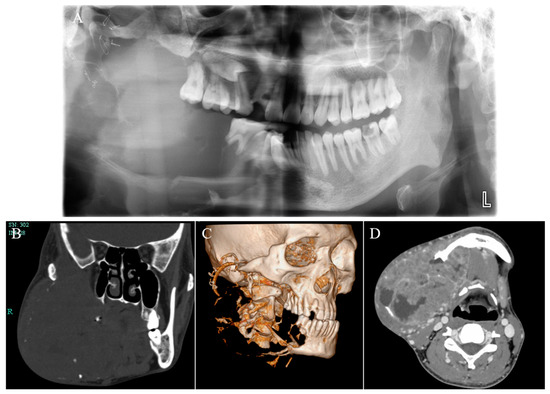

2. Case Report